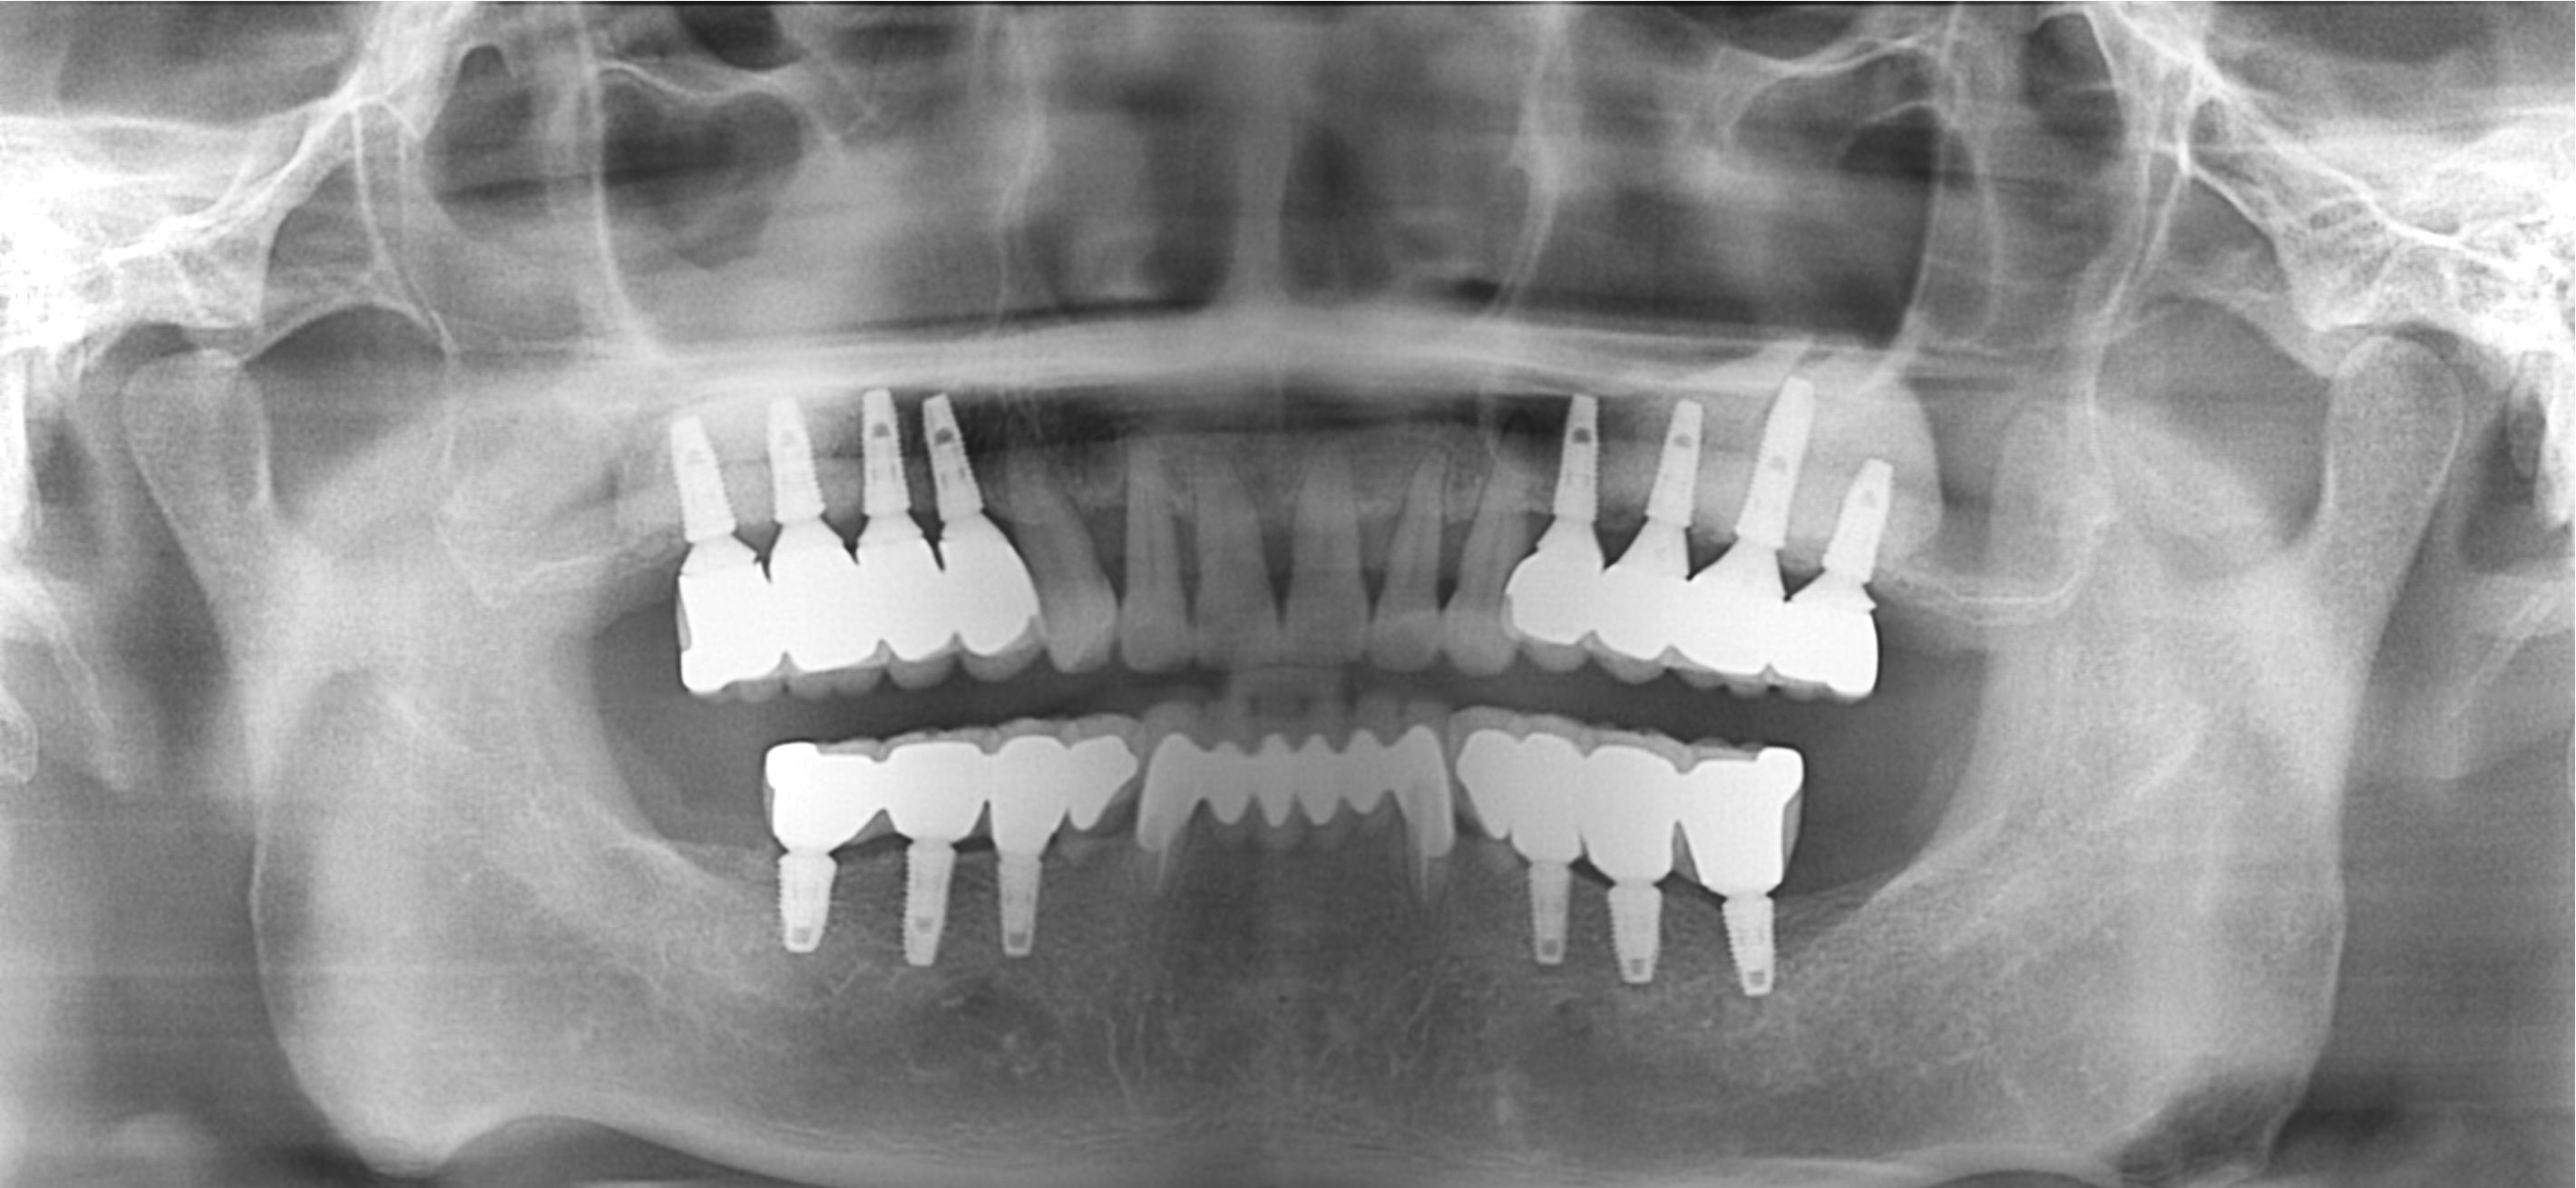

Before

After

상악동거상술 Sinus

중간과정 ▼